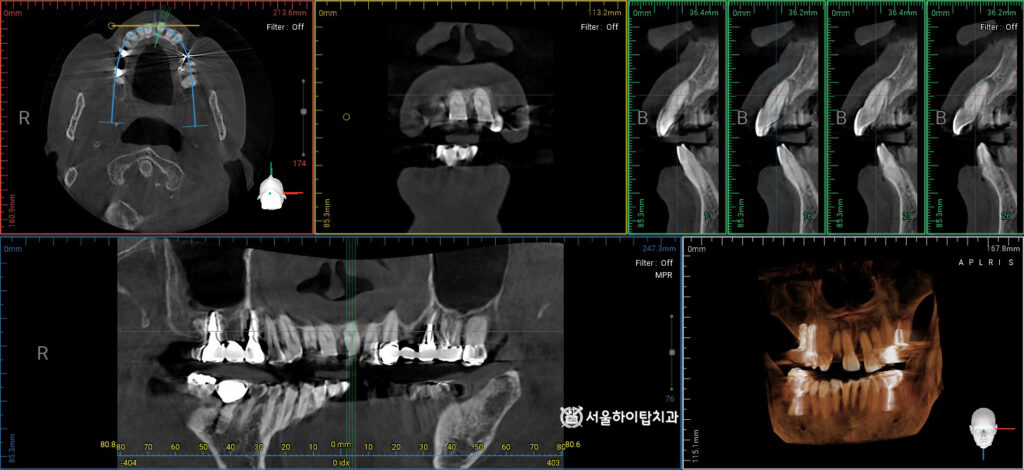

2. 정밀한 CT 모의 식립

현재는 치관이 완전히 파절된 상태이며,

치조골 소실이 동반되어 있습니다.

따라서 보존적 치료만으로는

장기 예후를 기대하기 어렵습니다.

이러한 경우에는 발치 후

골 재생 및 임플란트를 계획하는 것이

기능, 심미 회복 측면에서

합리적인 접근입니다.

이에 따라, 픽스처가 심어질 위치를

앞선 CT를 통해 사전에 확인하고,

잔존골의 높이, 밀도, 두께 등을

면밀하게 분석합니다.